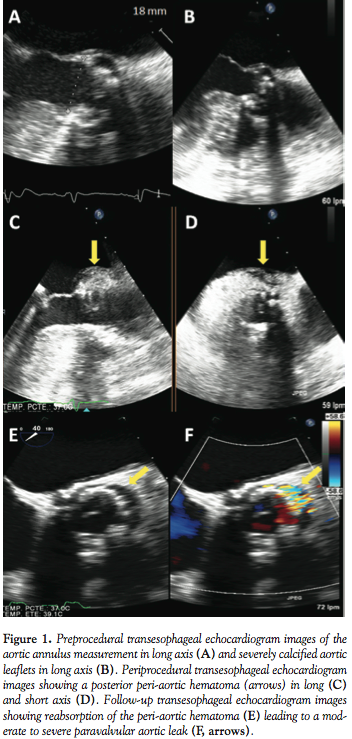

The procedure was done under general anesthesia with transesophageal echocardiogram (TEE) and angiography guidance. Preprocedural TEE showed an annulus size of 18 mm, prominent basal septal hypertrophy, and a heavily calcified valve (Figures 1A and 1B). A 23 mm Edwards-SAPIEN valve (Edwards Lifesciences, Inc) was selected for implantation by transfemoral approach. Via left femoral vessels, a 5 Fr pigtail was positioned in the ascending aorta and a temporary pacemaker was implanted in the right ventricle. Using a 5 Fr Amplatz left catheter (Cordis Corporation), the aortic valve was crossed with a Terumo straight wire, and exchanged for a stiff wire, which was positioned into the left ventricular apex via right femoral artery approach. A balloon valvuloplasty was first performed using a 20 mm balloon without any complications and the transcatheter heart valve was deployed during rapid pacing to 180 bpm. Aortogram and TEE subsequently confirmed adequate position of the bioprosthesis without paravalvular leak, and TEE imaging revealed a posterior peri-aortic hematoma (Figures 1C and 1D). By the end of the study, the hematoma remained stable, reaching dimensions of 15 x 20 mm with no flow outside the aorta by Doppler images and no noted pericardial effusion. The patient was extubated in the catheterization laboratory and transferred to the coronary care unit. A repeat TTE 2 days after the procedure showed reabsorption of the peri-aortic hematoma and a paravalvular leak grade mild to moderate (II/IV) in the same localization of the previous hematoma. The patient was discharged to home 5 days after the procedure clinically stable. Four days later, the patient came back with recurrent heart failure symptoms. TTE and TEE were performed, and showed a progression of the PAR grade judged as moderate to severe (vena contracta of 6 mm and a jet deceleration time of 150 ms; Figures 1E and 1F). The patient was discharged with medical treatment and was reviewed in the outpatient clinic 20 days later; she had no dyspnea or DPN at that time. One month later, she was re-admitted with minimal exertion dyspnea and new-onset atrial fibrillation. During the hospitalization, 2 consecutive balloon postdilations (BPD) were performed with 20 and 22 mm balloons, obtaining an increase in 1 mm of the inner diameter of the valve, but no improvement in aortic regurgitation grade. Nonetheless, the patient could be discharged with medical treatment and has remained stable with an adequate physical capacity during 6 months of follow-up.

TAVI is an emerging field for the treatment of severe AS in a high-risk population. Despite being less invasive than SAVR, TAVI nevertheless remains associated with serious complications. Left ventricular perforation, annulus rupture, and aortic dissection post TAVI have been previously described and are associated with a poor outcome.2 Peri-aortic hematoma has been recently described in 3 patients with a relatively benign outcome.3 As in our case, this complication was associated with advanced age, female gender, bulky-calcified aortic cusps that pushed against a small sinus of Valsalva, and significant basal septal hypertrophy. These anatomic features might lead to an excessive pressure to the posterior aortic root where the hematoma was initially seen. Oversizing aortic annulus might lead to aortic trauma, but valve size is systematically oversized by 2 to 5 mm with respect to the diameter of the aortic annulus.1 Contrary to previous cases where complete regression of the peri-aortic hematoma was noted in the TEE at follow-up, we describe reabsorption of the hematoma leading to a severe PAR. Although residual PAR following TAVI is usually mild, moderate or severe PAR can occur in about 10% of cases (5%-16%), and has been associated with worse acute and midterm outcomes.4 Incomplete stent expansion, particularly in the setting of severe calcific aortic annulus preventing complete sealing of the paravalvular space, has been suggested as a mechanism to explain PAR. Higher degree of valve calcification, malpositioning of the device, larger annulus, and prosthesis/annulus mismatch have been identified as predictors of moderate to severe aortic regurgitation following TAVI.5,6 However, this new mechanism of PAR, to our knowledge, has not been previously reported in the literature. Early recognition of this complication was possible because of intraprocedural TEE guidance. After a careful review of the case, medical treatment was the first choice. Due to the fact that the patient continued with symptoms, interventional closure of the paravalvular leak was considered a viable option,7,8 but BPD was estimated to be more appropriate in the context of a recent aortic hematoma and less risk of valve dislodgment. Thus, BPD was performed 2 months after the index procedure, and although a greater expansion of the stent containing the valve was obtained, the degree of PAR remained the same. Nonetheless, persistent clinical benefit was obtained with no further need for hospital admissions. Efficacy of BPD to reduce the degree of PAR immediately after valve implantation has been previously reported.9 Nevertheless, no data are available on the efficacy and safety of BPD for the treatment of severe PAR in the follow-up period, or in cases in which the presumed mechanism was initial oversizing.